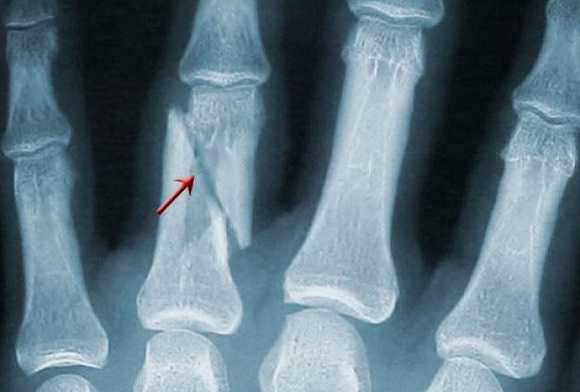

Для подагрического артрита характерно преимущественное поражение дистальных отделов стоп с преобладанием изменений в области I плюсне-фаланговых сочленений, реже изменения выявляются в мелких суставах кистей. При остром подагрическом артрите рентгенологические изменения, как правило, отсутствуют. Поэтому речь идет об изменениях, характеризующих хроническую стадию болезни. Типичным для хронического подагрического артрита является обнаружение узловых образований (тофусов) в костях в виде кистовидных просветлений и участков повышения плотности мягких тканей в области фаланг пальцев кистей и стоп. Деструкция костной ткани в виде эрозий, часто выявляемая при хроническом течении подагры, локализуется в основном на краях эпифизов костей и в дальнейшем распространяется на центральные отделы суставов.

Эрозии при подагрическом артрите имеют округлую или овальную форму, часто со склеротическим ободком. Склеротический ободок вокруг внутрисуставного тофуса создает типичный для подагрического артрита симптом «пробойника» (см. рис. 1).

Эрозии часто обнаруживаются в верхней и медиальной части плюсневой головки и часто в сочетании с вальгусной девиацией суставов. Типичным является асимметричность изменений (рис. 2).